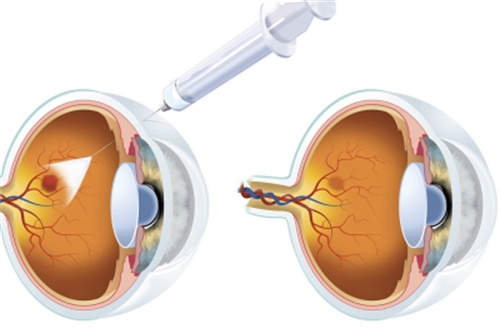

孙医生在玻璃体视网膜手术方面具有独特技术优势,采用国内外靠前的小创口玻璃体切割技术治疗复杂性视网膜脱离,手术成功几率达90%以上。

对于糖尿病视网膜病变患者,他创新性地结合抗VEGF药物注射与精密激光治疗,有效延缓病情进展。

典型玻璃体手术包含三个关键阶段:

术前准备:超全评估全身状况,定制个性化玻璃体替代方案

精细操作:在显微镜下完成视网膜前膜剥离、激光光凝等步骤

术后管理:采用特殊体位护理,配合***药物治疗